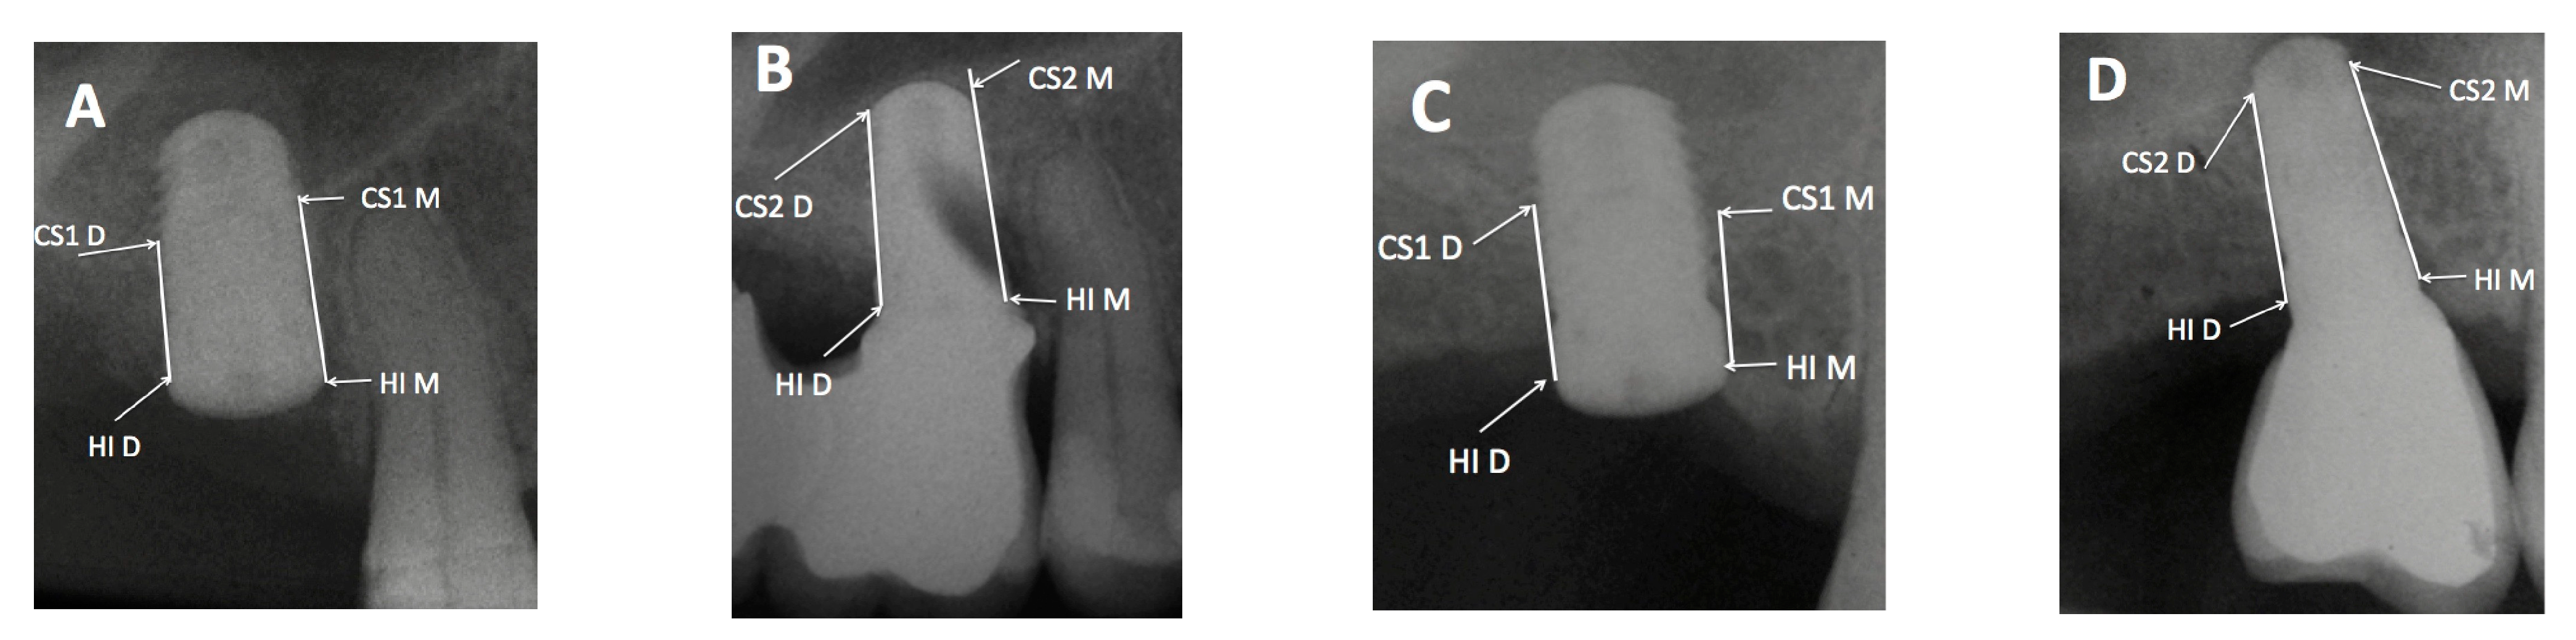

2.3. Relationship between the Maxillary Sinus Cavity and Implant Location

- -

- Sinus type A: implant is close to the mesial wall of the sinus (25% of cases);

- Sinus type B: implant is located in a flat sinus floor at some distance from the osseous walls and/or partitions. This was the most common situation representing 37.5% of cases;

- Sinus type C: implant is in contact with, or very close, to the distal sinus wall (12.5% of cases);

- Sinus type D: implant is very close to a bony wall at the mesial and distal aspects of the maxillary sinus or in contact with an Underwood septum, delimiting the maxillary sinus into different compartments (25% of cases).